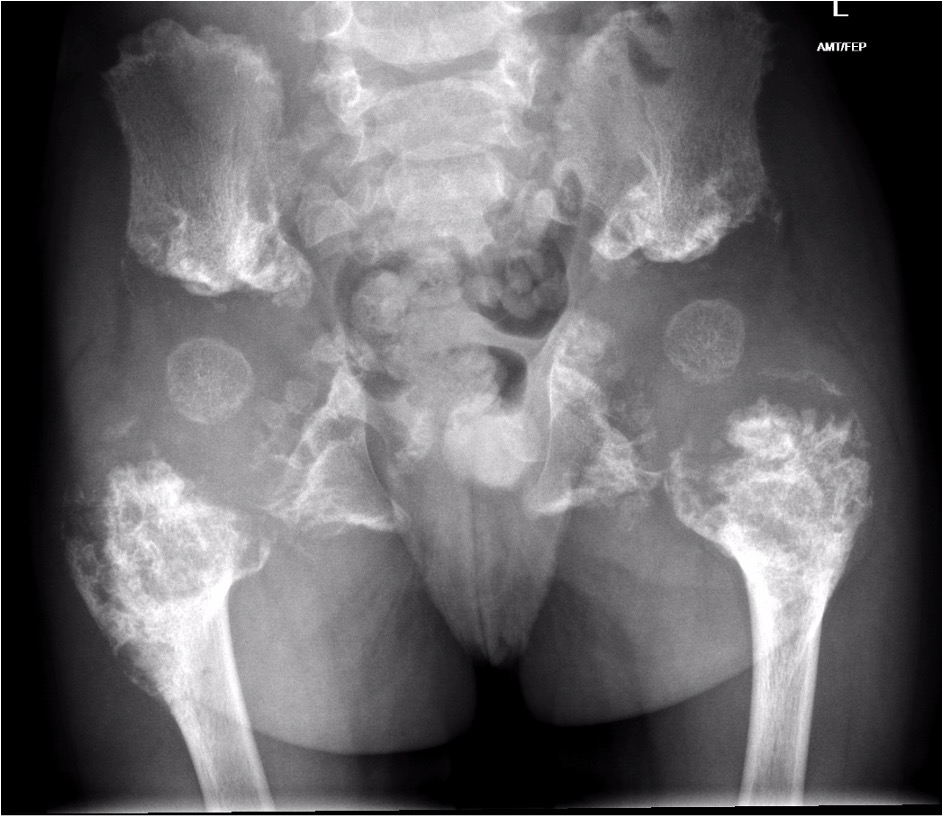

Metaphyseal changes of tubular bones

- normal epiphyses

- metaphysis adjacent to physis very broad and mildly scalloped

Erlenmeyer Flask Deformity

Jansens (Rare)

- most severe

- extensive calcification

- striking bulbous metaphyseal expansion long bones

Hips

- coxa vara